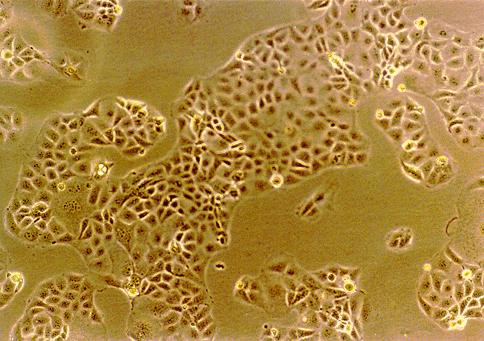

| Cell name | PLC/PRF/5 | ||||||||||||||||||

| Morphology | Epithelial-like. | ||||||||||||||||||

| Characteristics | Hepatoma cell line. Alexander cells. This cell line secretes HBs antigen. HLA-A 3302/ | ||||||||||||||||||

| Photo | ![]() Photo(x100) |